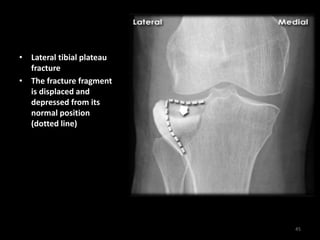

Tibial plateau fracture - AP

44

• Lateral tibial plateau

fracture

• The fracture fragment

is displaced and

depressed from its

normal position

(dotted line)